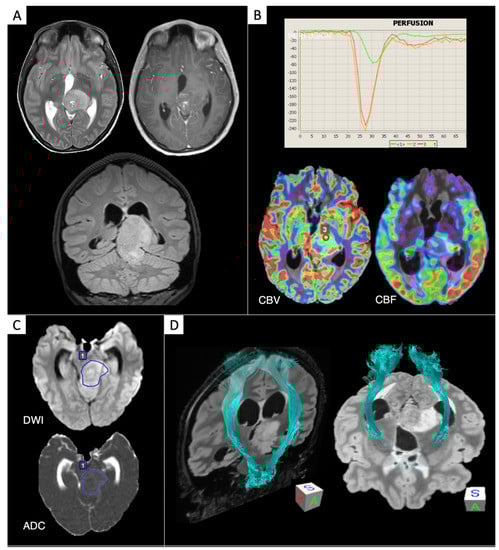

- Castellano, A.; Bello, L.; Michelozzi, C.; Gallucci, M.; Fava, E.; Iadanza, A.; Riva, M.; Casaceli, G.; Falini, A. Role of diffusion tensor magnetic resonance tractography in predicting the extent of resection in glioma surgery. Neuro Oncol. 2011, 14, 192–202. [Google Scholar] [CrossRef] [PubMed]

- Bello, L.; Gambini, A.; Castellano, A.; Carrabba, G.; Acerbi, F.; Fava, E.; Giussani, C.; Cadioli, M.; Blasi, V.; Casarotti, A.; et al. Motor and language DTI fiber tracking combined with intraoperative subcortical mapping for surgical removal of gliomas. NeuroImage 2008, 39, 369–382. [Google Scholar] [CrossRef] [PubMed]

- Bizzi, A. Presurgical mapping of verbal language in brain tumors with functional MR imaging and MR tractography. Neuroimaging Clin. N. Am. 2009, 19, 573–596. [Google Scholar] [CrossRef]

- Castellano, A.; Cirillo, S.; Bello, L.; Riva, M.; Falini, A. Functional MRI for surgery of gliomas. Curr. Treat. Options Neurol. 2017, 19, 34. [Google Scholar] [CrossRef]

- Sanvito, F.; Caverzasi, E.; Riva, M.; Jordan, K.M.; Blasi, V.; Scifo, P.; Iadanza, A.; Crespi, S.A.; Cirillo, S.; Casarotti, A.; et al. FMRI-targeted high-angular resolution diffusion MR tractography to identify functional language tracts in healthy controls and glioma patients. Front. Neurosci. 2020, 14, 225. [Google Scholar] [CrossRef]